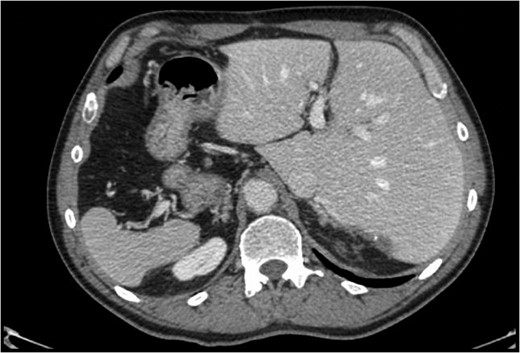

Situs inversus totalis (SIT) is a congenital condition consisting of a mirror image of transposition of the abdominal and thoracic organs occurring in about 1:5000 to 1:10 000 adults. We report on a 60-year-old male with a single colorectal liver metastasis in the Segment 7. The patients underwent a totally laparoscopic sub-segmentectomy. Intraoperative approach on a reverse posterior segment was difficult because of left-sided position of the liver. Postoperative course was uneventful and the patient was discharged after 5 days. To our knowledge, only a few cases of open liver resections in patients with SIT have been published. This is, therefore, the first case of laparoscopic liver resection for colorectal liver metastasis in a patient with SIT. We provide the readers with useful tips to perform minimally invasive liver surgery in such patients.

Situs inversus is a congenital condition with an incidence ranging between 1:1000 and 1:10 000 characterized by left-to-right transposition of one or more normally asymmetrical organs of the body. Situs inversus totalis (SIT) consists of a mirror-image transposition of the abdominal and thoracic viscera, which occurs in about 1:5000 to 1:10 000 adults [1]. Patients affected by SIT are usually completely asymptomatic, but they have more commonly major defects which can shorten their lifespan [1].

We herein present the case of a patient with a single colorectal liver metastasis with SIT providing the readers with useful information to approach this condition.